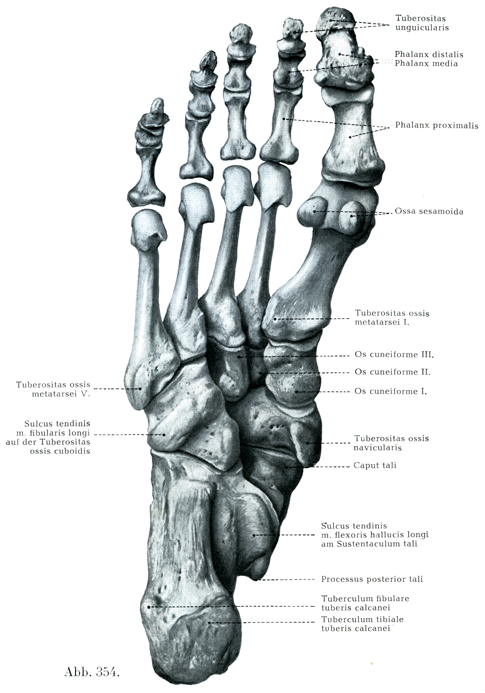

[図354]足の骨(右)足底面(6/7) 図353と同一のH. Virchow作製の標本(凍結骨格処理法によって,骨の相互の自然の間隔と正しい向きを保って組立てられている)